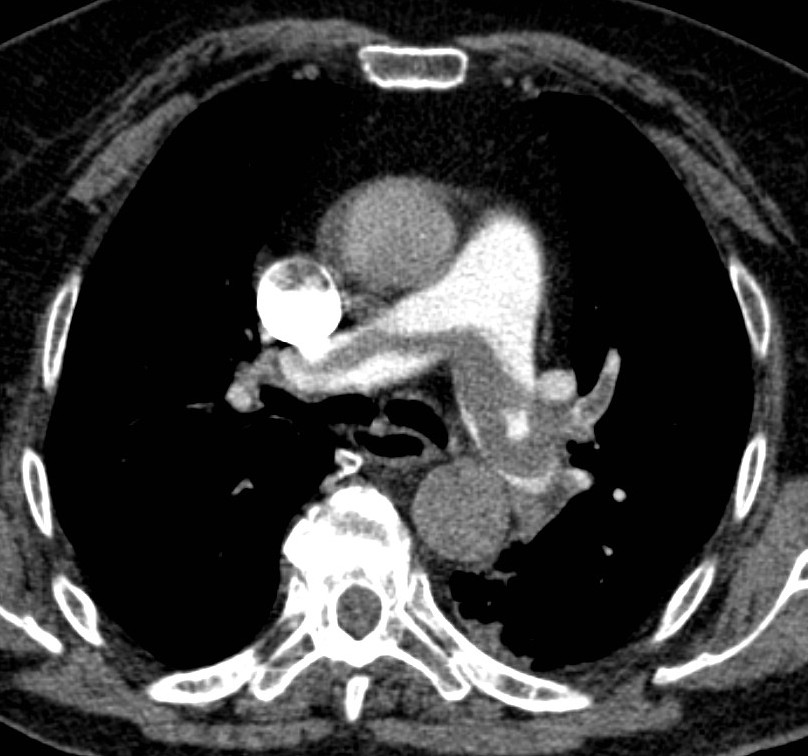

25. Massive pulmonary embolism. CT angiography (axial image and coronal reconstruction)

84 year old woman: dyspnea, elevated D-dimer.

Pulmonary embolism, riding embolus in the pulmonary trunk and in both pulmonary arteries + in smaller branches bilaterally as well. Contrast filling defects are seen according to the emboli.